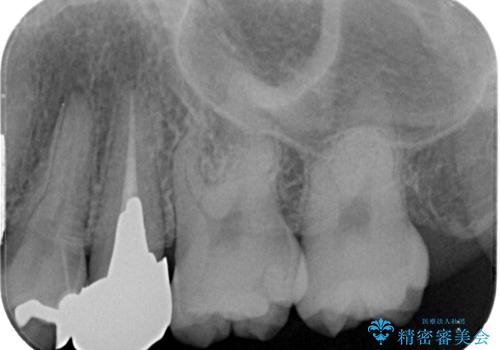

- 笑った時に目立つ銀歯を治したいとのことで来院された患者様です。検査の結果、オールセラミッククラウンによる補綴治療を行っていくことにしました。

拡大鏡視野下で銀歯を外し、オールセラミッククラウンに適した形に整えました。

歯と歯茎の間に圧排糸と言われる糸を入れてシリコーン印象材にて型どりをしました。

また、根管治療、土台のやり替えについてご提案しましたが、患者様のご希望により被せもののみのやり替えとなっています。